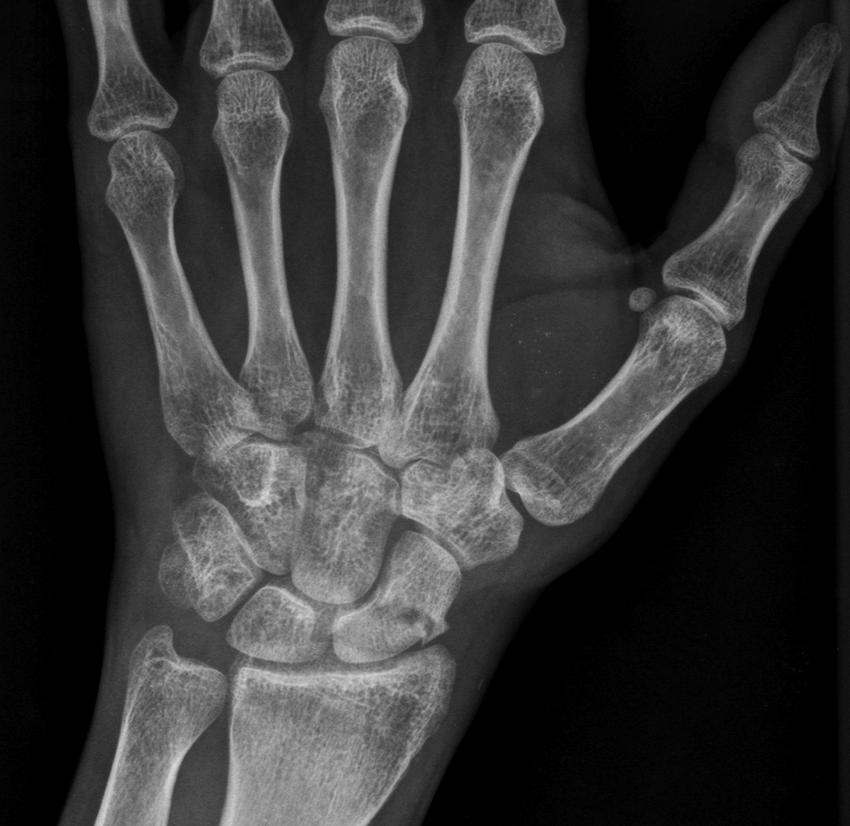

1 carpal fracture? Risks?

Scaphoid, risks of nonunion/AVN

Most common scaphoid fx location? Complications?

Middle/waist followed by proximal pole and distal pole Complications: Osteonecrosis, nonunion, SLAC (scaphoid lunate advance collapse)